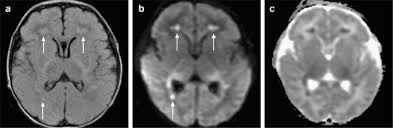

Lesions similar to cytotoxic edema, and lesions similar to vasogenic edema. Seizure, altered sensorium, fever frontal and temporal lobes, rarely extratemporal t2 hyperintensity, restricted diffusion, sometimes. Herpes encephalitis is the most common sporadic encephalitis in the united states and other industrialized countries .occurring as either a primary infection with herpes simplex virus or as a reactivation of latent virus, herpes encephalitis causes significant morbidity and mortality .early intervention with acyclovir significantly improves outcome; The clinical syndrome is often characterized by the rapid onset of fever, headache, seizures, focal neurologic signs, and impaired consciousness 1 . Having said that, mri with contrast is considered the most sensitive imaging modality, and findings are present in over half of individuals 8. The patients with the former type of lesions had fulminating disease, and were in severe clinical condition. Herpes simplex encephalitis occurs as 2 distinct entities: 4 it was found that, rather surprisingly, varicella zoster virus (vzv), the cause of chickenpox and herpes zoster, was the most frequently detected virus at 29%, with hsv and enteroviruses accounting for 11% of cases. Two subtypes are recognized which differ in demographics, virus, and pattern of involvement. (1)department of radiology, ankara numune education and research hospital, ankara, turkey. Neonatal herpes simplex encephalitis is caused by vertical transmission of infection during passage from birth canal with diffuse cerebral involvement within the first month after birth; As the older term limbic encephalitis implies, the most common location of involvement is the mesial temporal lobes and limbic systems, typically manifested by cortical thickening and increased t2/flair. In patients with herpes encephalitis, two distinct types of diffusion imaging findings (on b =1000 s/mm 2 images, and adc maps) were noted:

We present mri findings of two cases of herpes simplex encephalitis (hse) confirmed by pcr analysis, focusing on the serial changes after acyclovir therapy: 4 it was found that, rather surprisingly, varicella zoster virus (vzv), the cause of chickenpox and herpes zoster, was the most frequently detected virus at 29%, with hsv and enteroviruses accounting for 11% of cases. mri findings of herpes simplex encephalitis. For viral infection of the meninges, please refer to the general article on viral meningitis, and, for a broad view on the curriculum of infections of the central nervous system, refer to cns. The patients with the former type of lesions had fulminating disease, and were in severe clinical condition. The kappa value for interobserver agreement on rating the scans as normal or abnormal was good (0.65) for ct and moderate (0.59) for mri. Noguchi t, yoshiura t, hiwatashi a, et al. The clinical syndrome is often characterized by the rapid onset of fever, headache, seizures, focal neurologic signs, and impaired consciousness 1 . The patients with the former type of lesions had fulminating disease, and were in severe clinical condition. Specific diagnosis often requires pcr. As the older term limbic encephalitis implies, the most common location of involvement is the mesial temporal lobes and limbic systems, typically manifested by cortical thickening and increased t2/flair. In patients with herpes encephalitis, two distinct types of diffusion imaging findings (on b =1000 s/mm 2 images, and adc maps) were noted: A recent study in finland also used pcr to detect various viruses in the csf of over 3000 patients who had infections of the cns including encephalitis, meningitis, and myelitis.

(1)department of radiology, ankara numune education and research hospital, ankara, turkey. article in japanese yoshioka a, hirose g, tsukada k, oda r, kosoegawa h. Two subtypes are recognised which differ in demographics, virus, and pattern of involvement. Seizure, altered sensorium, fever frontal and temporal lobes, rarely extratemporal t2 hyperintensity, restricted diffusion, sometimes. Encephalopathy from herpes simplex encephalitis (hse). Specific diagnosis often requires pcr. Having said that, mri with contrast is considered the most sensitive imaging modality, and findings are present in over half of individuals 8. We present mri findings of two cases of herpes simplex encephalitis (hse) confirmed by pcr analysis, focusing on the serial changes after acyclovir therapy:

The patients with the former type of lesions had fulminating disease, and were in severe clinical condition. The diagnosis of hse is based on laboratory investigations, magnetic resonance (mr) imaging findings, electroencephalogram and, occasionally, a biopsy. Herpes encephalitis is the most common sporadic encephalitis in the united states and other industrialized countries .occurring as either a primary infection with herpes simplex virus or as a reactivation of latent virus, herpes encephalitis causes significant morbidity and mortality .early intervention with acyclovir significantly improves outcome; Herpes simplex (hsv) encephalitis is the most common cause of fatal sporadic fulminant necrotising viral encephalitis and has characteristic imaging findings. In patients with herpes encephalitis, two distinct types of diffusion imaging findings (on b =1000 s/mm 2 images, and adc maps) were noted: Relapse of encephalitis occurs in up to 10% of patients, manifested by recurrent symptoms, clinical and mri findings, and the presence of herpes simplex virus type 1 dna in the cerebrospinal fluid (csf). In children older than 3 months and in adults, hse is usually localized to the temporal and frontal lobes and is c. In patients with herpes encephalitis, two distinct types of diffusion imaging findings (on b =1000 s/mm 2 images, and adc maps) were noted: Herpes simplex (hsv) encephalitis is the most common cause of fatal sporadic fulminant necrotizing viral encephalitis and has characteristic imaging findings. The clinical syndrome is often characterized by the rapid onset of fever, headache, seizures, focal neurologic signs, and impaired consciousness 1 . We present mri findings of two cases of herpes simplex encephalitis (hse) confirmed by pcr analysis, focusing on the serial changes after acyclovir therapy: Two subtypes are recognised which differ in demographics, virus, and pattern of involvement. Despite advances in antiviral therapy over the past 2 decades, herpes simplex encephalitis (hse) remains a serious illness with significant risks of morbidity and death.